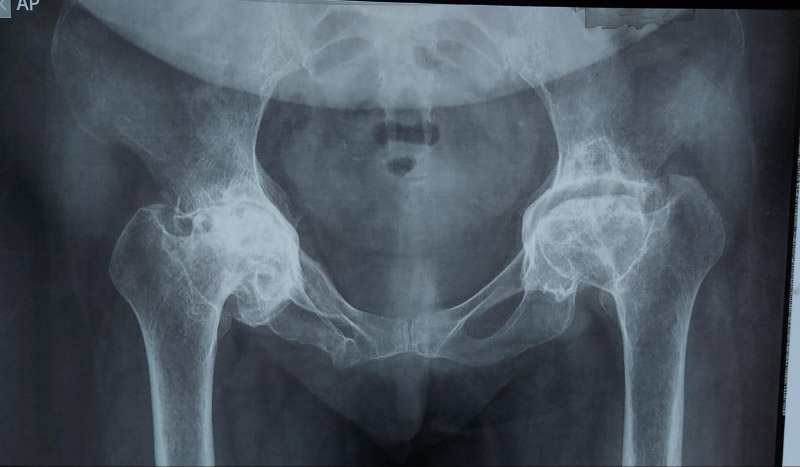

Giai đoạn 4 – Nghiêm trọng: Mất hoàn toàn khe khớp, xuất hiện gai lớn, xương đùi biến dạng nghiêm trọng.

Mất hoàn toàn khe khớp

Khe khớp mất hoàn toàn, xương đùi biến dạng nghiêm trọng

Biến dạng hai bên khớp

Biến dạng nghiêm trọng cả 2 bên xương đùi, hoại tử đến mạch khớp hông